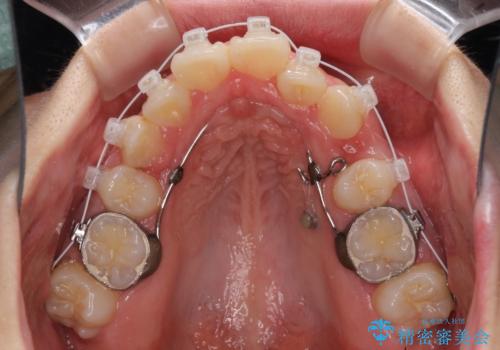

著しい叢生と顎骨のズレ ワイヤー装置による抜歯矯正

- 矯正装置

- 審美装置

- 前歯の著しい叢生や八重歯を気にして来院された患者様です。

上下の顎がずれており、上下の正中は歯1本分の差がありました。

上下左右の小臼歯4本を抜歯し、極力正中を合わせるように矯正治療を始めていくこととしました。

咬み合わせの乱れが著しく、治療途中で一部反対咬合となってしまいました。

アンカーなどをうまく使用して、3年の期間を要してきれいに仕上げることができました。